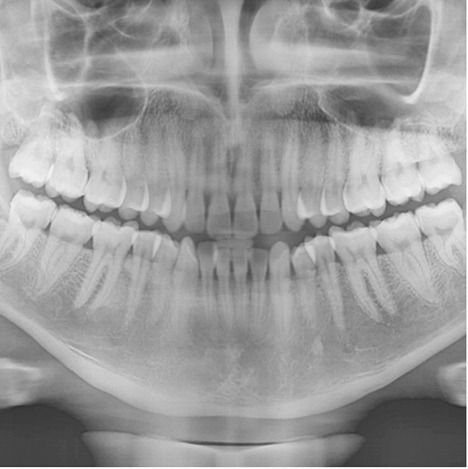

Ein Schwerpunkt liegt in der Implantologie, mit der wir sowohl festsitzenden als auch herausnehmbaren Zahnersatz ermöglichen. Auch operative Eingriffe wie die Entfernung von Weisheitszähnen, Zystenbehandlungen, Wurzelspitzenresektionen oder Zahntransplantationen gehören zu unserem Leistungsspektrum. Zudem führen wir Knochenaufbauverfahren, Parodontalchirurgie sowie die Behandlung von Kiefergelenksbeschwerden (CMD) durch.

- Operative Entfernung von Weisheitszähnen

- Zystenbehandlung an Wurzelspitzen und Entfernung von Kieferzysten

- Wurzelspitzenresektion

- Zahntransplantationen